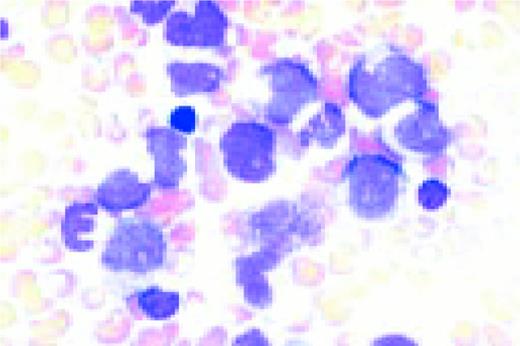

Macrocytosis. Pernicious anemia. Peripheral blood in a patient showing a large lymphocyte (top), macrocytosis and an orthochromic megaloblast (bottom). Nuclear-cytoplasmic disproportion is noted in the latter as is beaded nuclear chromatin.FIG122

Slide E27